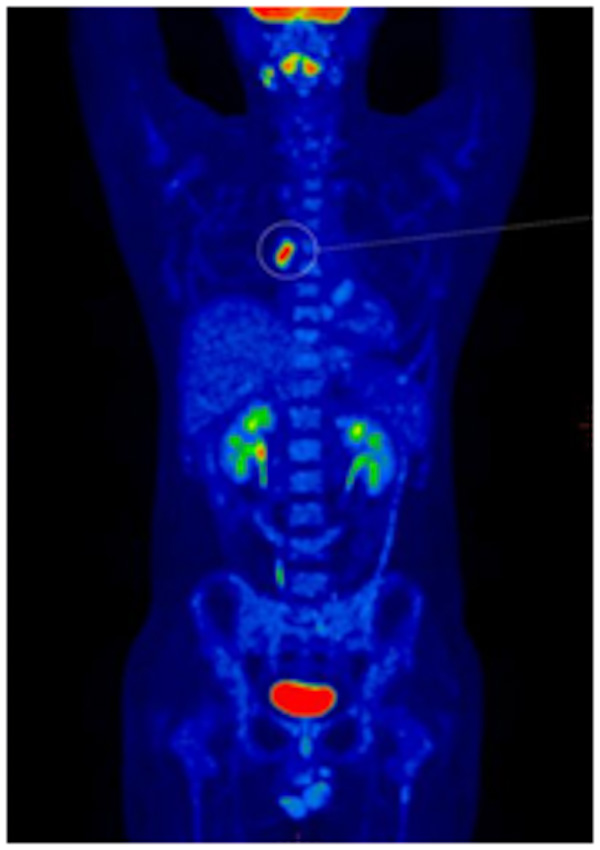

在PET-CT幫助黃先生找到所有淋巴瘤的病灶后,柳州市人民醫(yī)院血液內(nèi)科醫(yī)師們“對(duì)癥下藥”,患者經(jīng)過(guò)4周期化療后再次到核醫(yī)學(xué)科行PET-CT顯像。

治療后PET-CT顯像提示全身多發(fā)淋巴結(jié)較前明顯縮小、數(shù)量減少,部分可見(jiàn)低度腫瘤活性存在;兩側(cè)胸腔極少量積液,較前明顯吸收,取得了良好的療效。